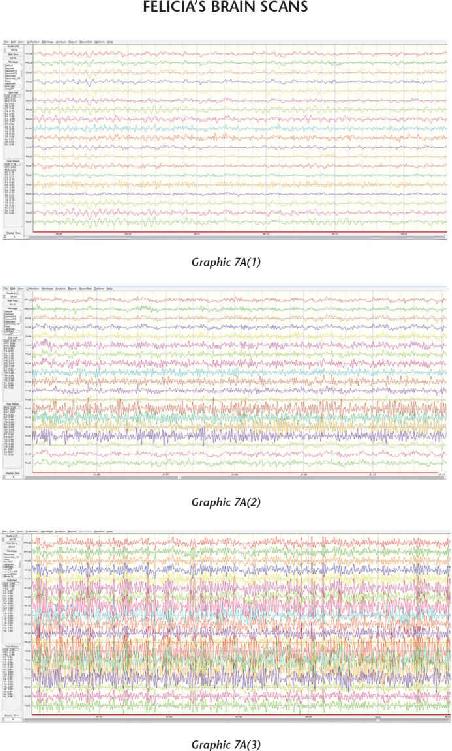

We have thousands and thousands of brain scans that prove those changes were not just imagined in their minds but actually took place in their brains. Several of the students we measured accomplished those changes within four days (the length of our advanced workshops). The scientific teams I’ve assembled have taken brain scan recordings using quantitative electroencephalogram (EEG) measurements before and after workshops as well as real-time measurements during the meditations and practices themselves. I was not only impressed with the changes, but shocked by them—they were that dramatic.

The brains of our students function in a more synchronized and coherent fashion after participating in the advanced retreats around the world. This increased order in their nervous systems helps them get very clear about a future they can create, and they are able to hold that intention independent of the conditions in their external environment. And when their brains are working right, they are working right. I will present scientific data that shows how much their brains improved in just a few days—which means you can do the same for your brain.

At the end of 2013, something mysterious started occurring. We started seeing brain scan recordings that puzzled the researchers and neuroscientists who came to our events to study my work. The high amount of energy in the brain that we were recording while a student was in certain meditations had never been recorded up until this point. And yet we were seeing these off-the-charts readings again and again.